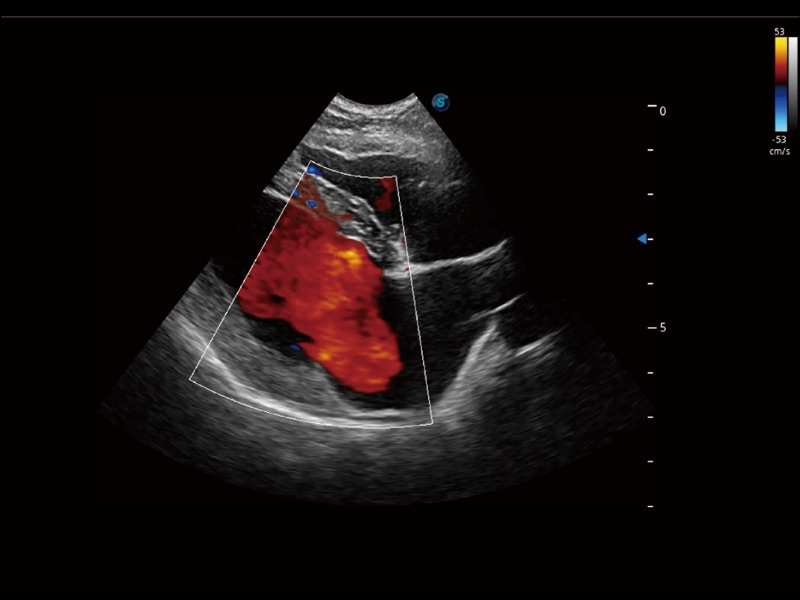

(犬)左室长轴血流

(犬)髂动脉血流